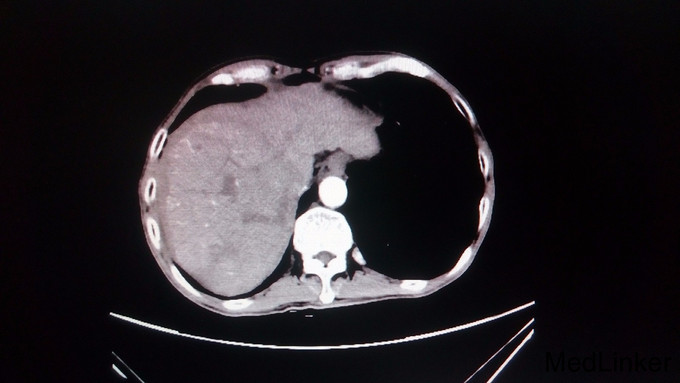

主诉:消瘦、乏力半年余 病史:患者自诉半年来体重下降近6KG,伴乏力,无其他不适。1周前至当地医院检查,腹部CT提示肝内巨大肿块,为进一步治疗前来就诊。

查体:未见明显异常 辅助检查;AFP424.4ug/L,CA199 162.3ug/L,乙肝小三阳白蛋白31.5g/L,转氨酶及胆红素未见明显异常。腹部CT提示肝硬化、脾大,食管远端胃底黏膜下静脉曲张,肝右叶巨大混杂密度影。考虑巨块型肝癌。

诊断:1、乙肝 2、肝硬化。3、巨块行肝癌。 处理:根据患者肝功能,拟行开腹右三页切除术。向患者及家属说明手术相关风险及费用。最终放弃治疗。

随访:无 讨论:患者巨大型肝癌,占据肝右叶及左肝内叶。但患者肝功能尚可,手术尚可一搏。只是具体还要考虑到剩余肝脏是否足够。请问具体怎么来判断残余肝脏是否能够满足人体需要而不发生肝衰竭呢?